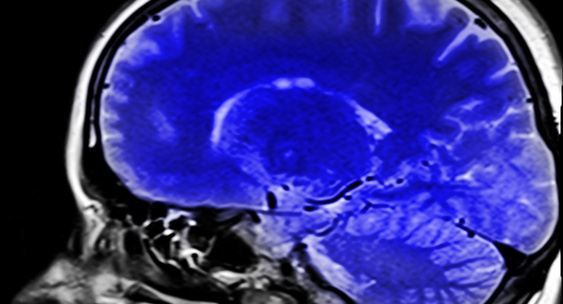

Radiology: избыток железа в мозге может увеличивает риск деменции

Учёные из Университета Джонса Хопкинса обнаружили, что повышенное содержание железа в определённых зонах мозга связано с риском когнитивных нарушений задолго до появления первых симптомов.Proulyanovsk

Работа велась в рамках долгосрочного проекта BIOCARD, где пожилые добровольцы без признаков деменции регулярно проходили когнитивные тесты и МРТ-картирование количественной восприимчивости.Proulyanovsk

Анализ показал: именно повышенное содержание железа на старте исследования было связано с удвоенным риском развития проблем с памятью и мышлением.Proulyanovsk

Авторы отмечают, что в будущем измерение уровня железа в мозге может стать не только инструментом ранней диагностики риска деменции, но и потенциальным направлением терапии.Proulyanovsk